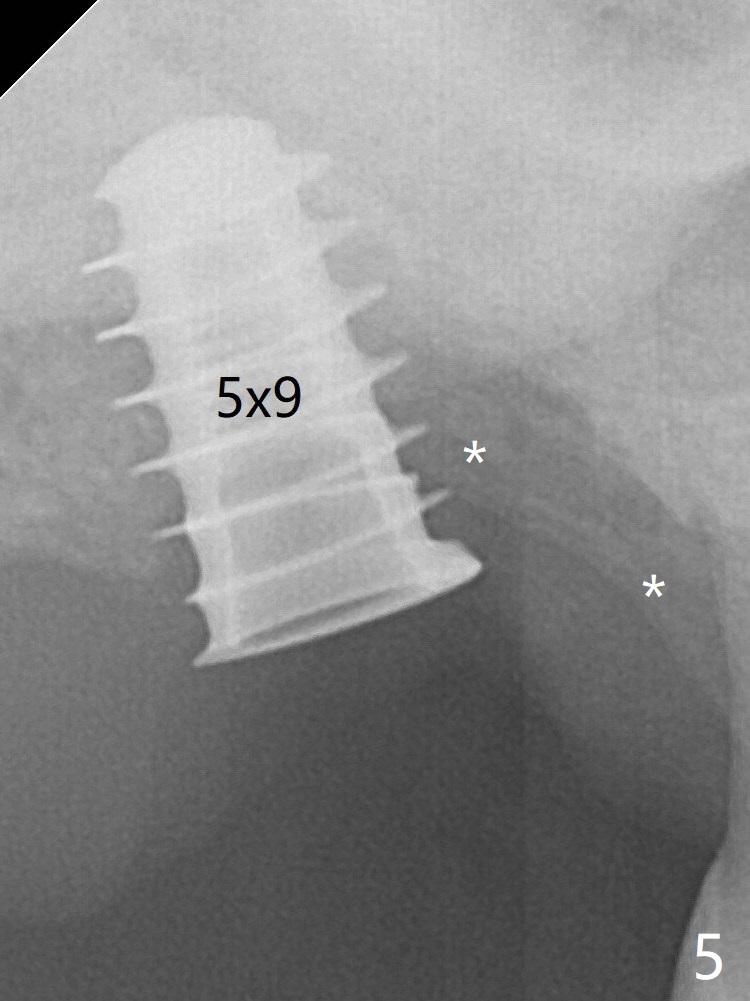

Trajectory is found to be off when 5x9 mm dummy FC implant is placed with stability (Fig.5 (*: defect)). The final implant, Magicore (5x7(3)mm, >29 Ncm), appears to be placed too deep for restoration (Fig.6,7); a screw retained crown may be a solution. PRF membrane and Vanilla (allograft) are used for sinus lift (no sinus membrane perforation). Following Vanilla graft in the socket gap (Fig.6 *), another piece of PRF membrane is used to cover socket opening. The membrane is fixed in place with suture and periodontal dressing. When a FC implant is placed too deep, a pair abutment with longer cuff will solve the problem. With Magicore, the diameter of abutment is unable to change. The implant seems to have osteointegrated 3.5 months postop (Fig.8). After change to 4.3x5 mm solid abutment and mesial surface adjustment, impression is taken for early loading because of removal of #14 implant. In fact the patient is satisfied with mastication improvement at #2 later on.